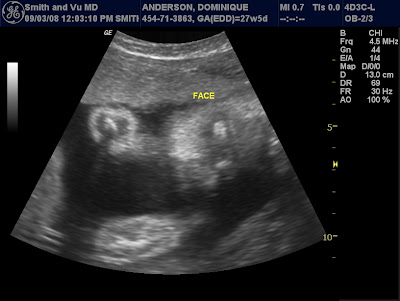

Well, the doctor did some measurements and according to Cheyenne's growth and development, I'm actually ahead of schedule. So, my due date has moved from November 28th to November 18th. Maybe I'll get to have some turkey after all.

Currently, she weighs 2 lbs and a few ounces.

Snapshot of her face